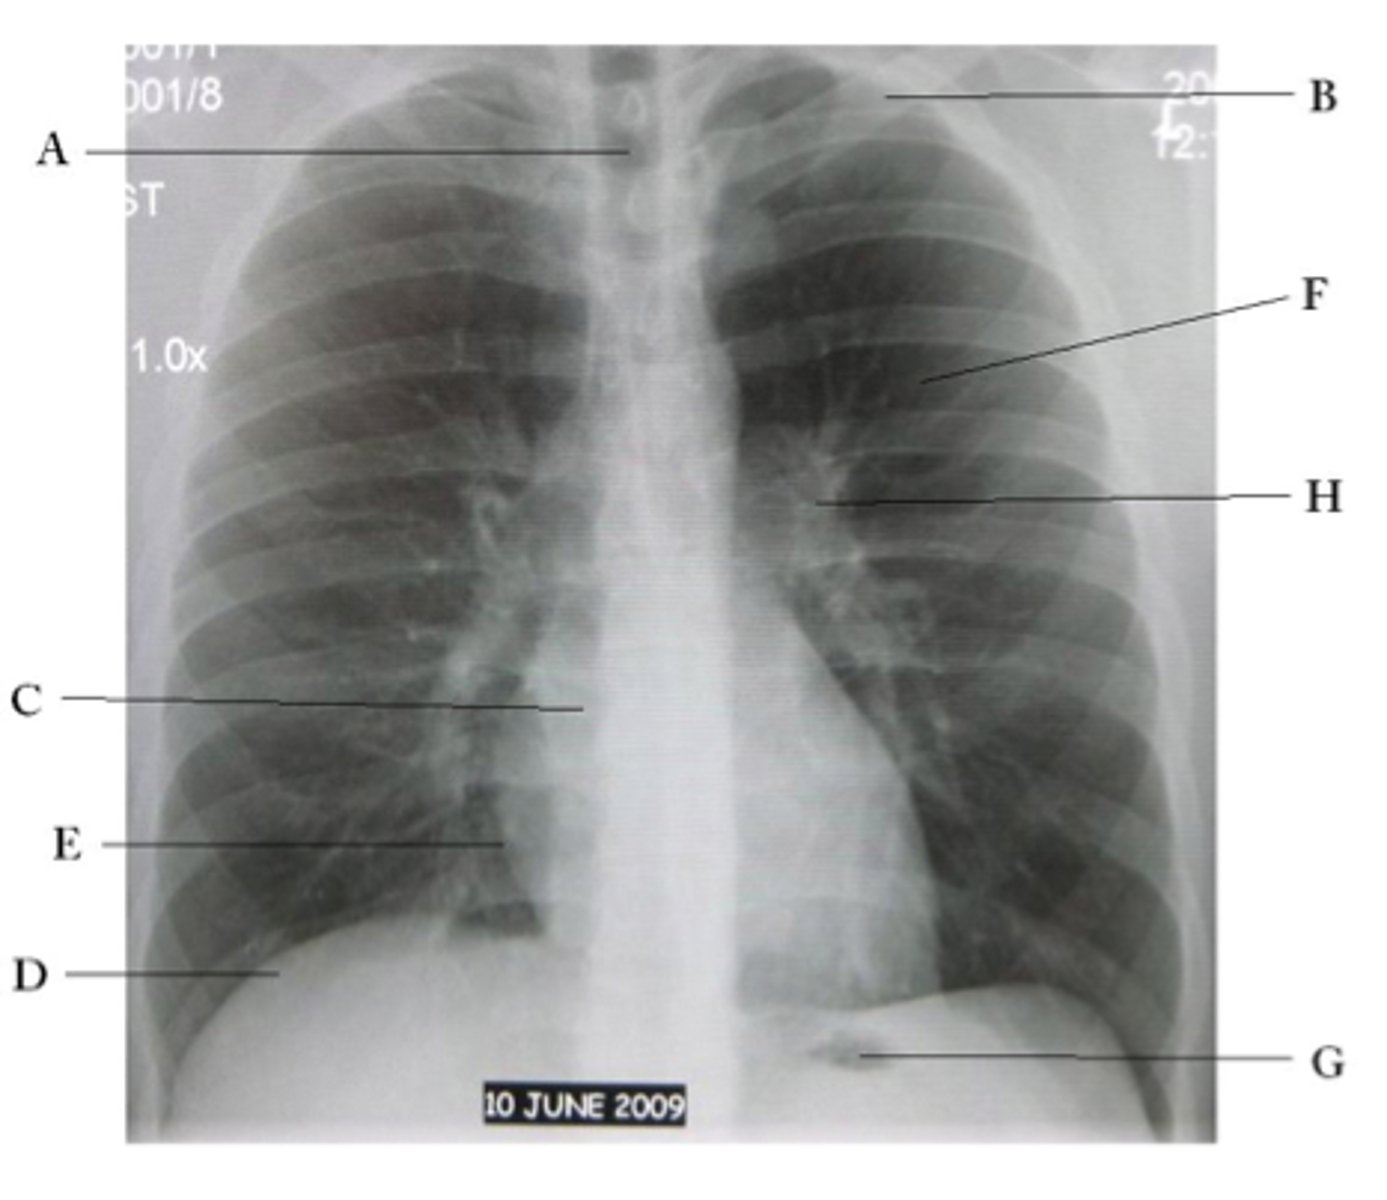

Bilateral pleural effusion

Silhouette sign right cardiac border, RML